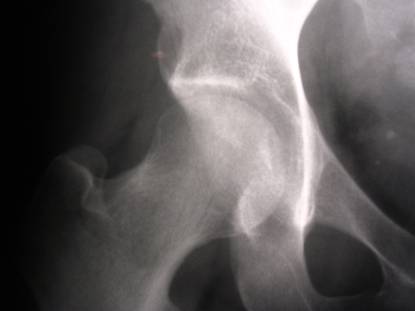

Left hip pain